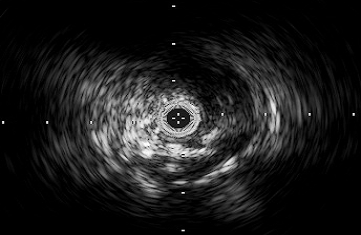

where is a set of available frames in a particular IVUS sequence. We can then locate the artifacts’ coordinates by subtracting the artifact zones from every frame, as in [5]. Figure 1(b) and Figure 1(f) show the resulted minimum image in B-mode and polar frame respectively.

Another type of artifact that we can detect using Eq.1 is the calibration square artifact. These small squares have a very bright constant intensity in all frames that remains bright in the minimum image. In several longitudinal cuts of the IVUS volume the effects of these artifacts are revealed as horizontal lines. Figure 1 illustrates both the artifacts and the resulting image after removing them.